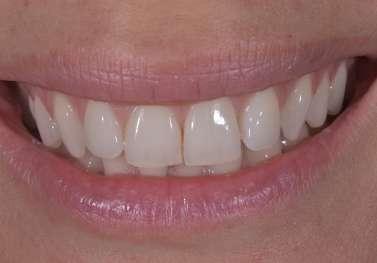

Trattamento di carie cervicale di elemento 1.5 con laser a Erbio

1 2

Paziente femmina, 38 anni che presenta carie cervicale dell’elemento 1.5. Gengivectomia con manipolo angolato, tip in zaffiro con diametro di 400 μm, lunghezza 12 mm, 2.4 W, 20 Hz, 120 mJ E per impulso, potenza di picco 750 W, densità di potenza media 659 W/cm2, densità di potenza di picco 205,860 W/cm2, energia totale 432 J, larghezza impulso 160 μs, distanza tip-tessuto 1 mm, 50% acqua, 50% aria, tempo totale di trafamento 180 sec. Impostazioni dello smalto: manipolo angolato, tip in zaffiro diametro 800 μm, lunghezza 12 mm, totale energia 810 J, ampiezza dell’impulso 160 μs, distanza tip-tessuto 1 mm, 100% acqua, 70% aria, tempo di trafamento totale 180 sec.

Fig. 1 – Cavità su 1.5 Fig. 2 – Particolare della cavità del dente 1.5 Fig. 3 – Preparazione Laser Er:YAG Pluser con lunghezza d’onda di 2940 nm di LAMBDA DoctorSmile, Italia. Fig. 4 – Particolare della cavità dopo gengivectomia Fig. 5 – Particolare della cavità completata dopo la preparazione della dentina Fig. 6 – Restauro finale in composito (Asteria Tokuyama, Japan)